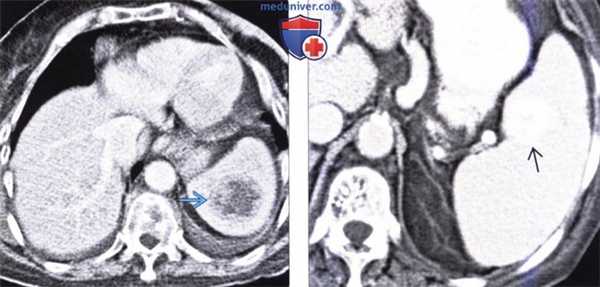

(Слева) На аксиальной КТ с контрастным усилением определяется большое объемное образование низкой плотности, которое было расценено как метастаз меланомы. Метастазы меланомы, как и некоторых других опухолей, могут выглядеть кистозными и ошибочно приниматься за абсцесс селезенки.

(Справа) На аксиальной КТ с контрастным усилением у пациентки, страдающей раком яичника с метастатической диссеминацией, определяются ограниченные скопления асцитической жидкости или многокамерные кистозные метастазы по брюшине, которые деформируют контур печени и селезенки. Визуализируется также несколько метастазов в паренхиме селезенки.